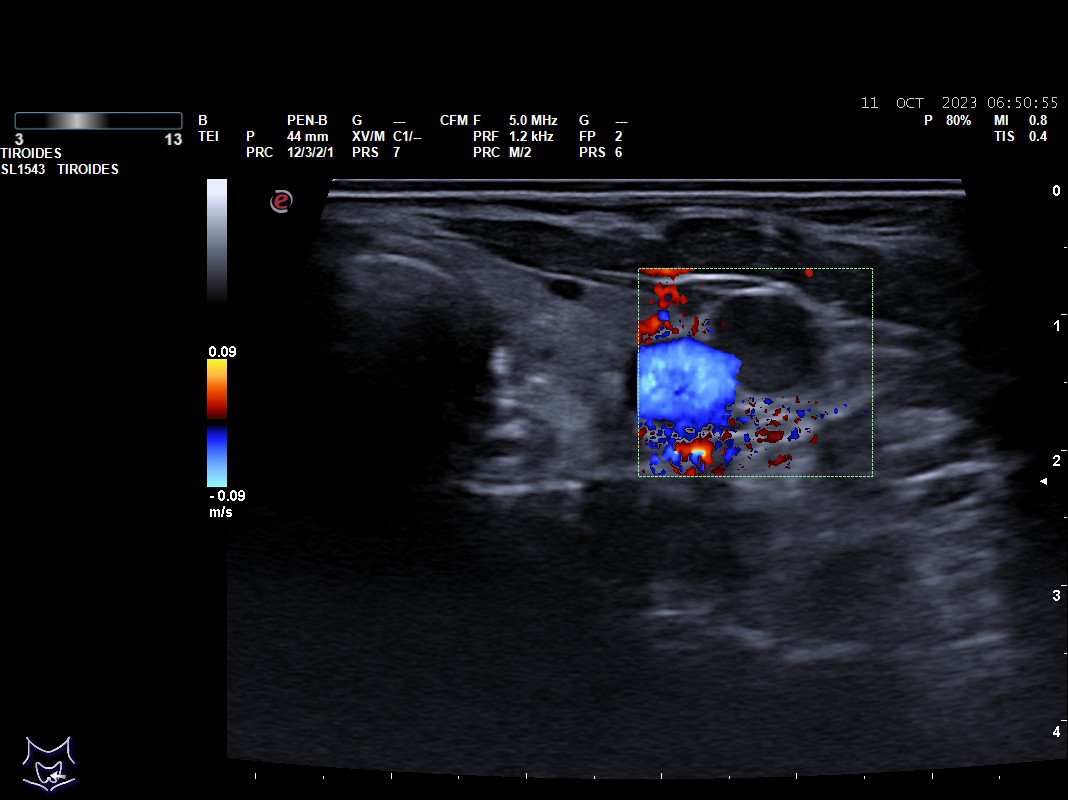

Hallazgos ecográficos: nódulos tiroideos subcentimétricos sin cambios, yugular interna izda con contenido discretamente hiperecogénico que no capta Doppler y colapsabilidad incompleta.

Se deriva a urgencias es valorada por cirugía vascular quienes describen la presencia del trombo sin poder precisar su final y se ingresa a la paciente ya que el servicio de radiología no considera realizar en ese momento el estudio pertinente.